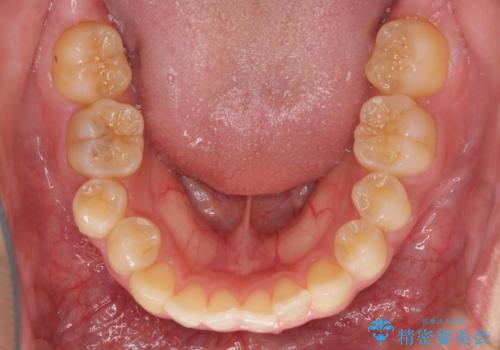

海外勤務中のインビザラインによる矯正治療

- 前歯のクロスバイトを気にして来院され患者様です。

治療期間が世界的な感染症の流行時期と重なったため、海外と日本での往来が困難となり、治療継続が懸念されました。

それでも、しっかりとマウスピースを装着してくださったので、大きなトラブルもなく治療を終えることができました。